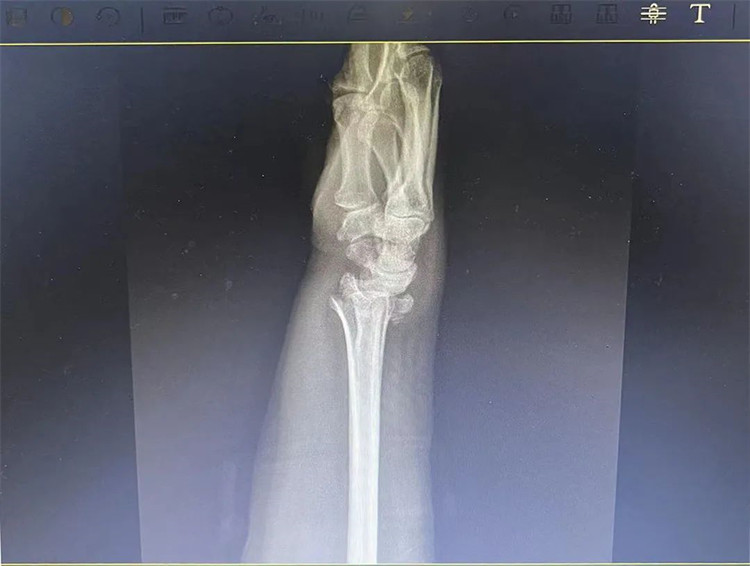

患者老年女性,50多歲,在騎電動車停下時因電動車倒下,右手著地,當(dāng)即感覺,右腕及骶尾部腫痛伴右關(guān)節(jié)畸形、活動受限,急來我院就診。門診醫(yī)師結(jié)合病史、查體及輔助檢查后,診斷為:右橈尺骨遠端骨折、骶尾部挫傷并收入住院部。